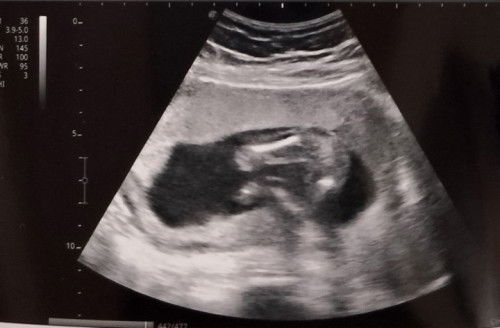

Lagi nakanganga si baby. Nag iipon din ng gatas/laway lagi sa bibig

Hello mga momsh, ask ko Lang Kung may Naka experience din po sa inyo na lagi nakanganga si baby? Wala naman Siya sipon ay ubo. Pero concern ko is yung parang may tunog sa may lalamunan nya, hilig nya din kasi mag ipon gatas or laway sa bibig. Tas minsan naman pagkagising nya parang tuyot yung lalamunan nya Kaya umiiyak. Advise naman po. TIA! #1sttimemom #1stbaby